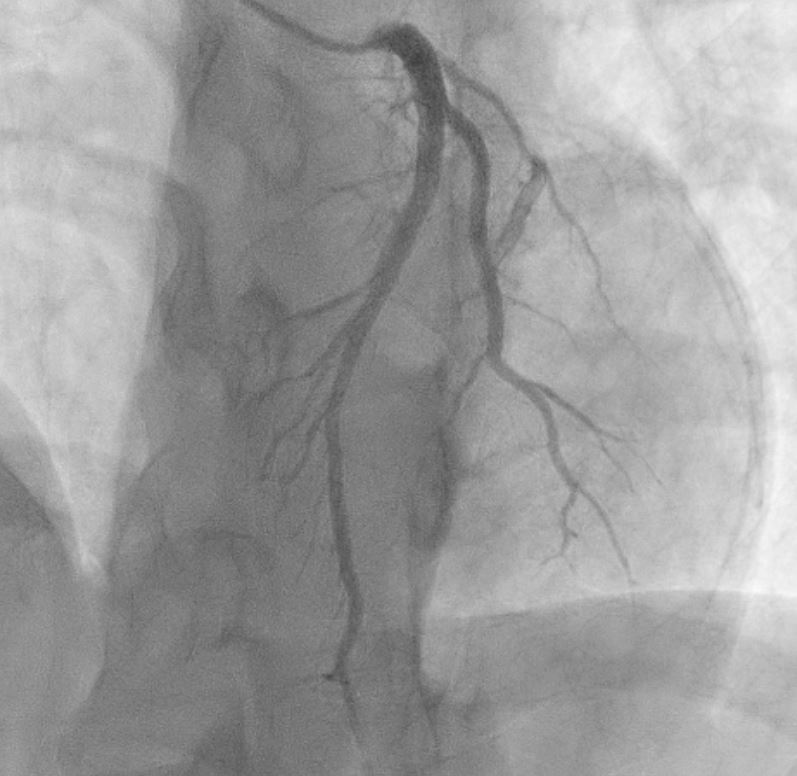

Proceeded with Primary PCI that revealed normal coronaries with mid LAD myocardial bridging . ST elevation resolved in cath lab.